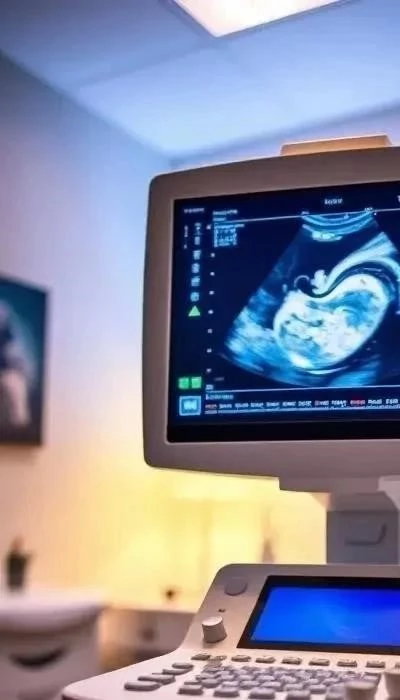

Визуализация развития: что показывает УЗИ эмбриона на разных сроках

Ультразвуковое исследование (УЗИ) – бесценный инструмент для визуализации удивительного процесса развития эмбриона внутриутробно. Это первое «окно» для наблюдения за формированием новой жизни, подтверждения беременности и оценки её хода. Ранние УЗИ важны для мониторинга критических этапов органогенеза.

Уже к 5-6 акушерским неделям на УЗИ видно плодное яйцо и желточный мешок. К 6-7 акушерским неделям различим эмбрион, напоминающий «зернышко», и можно зарегистрировать его сердцебиение. Это ключевой признак жизнеспособности, подтверждающий активное формирование органов.

Как правило, первое плановое ультразвуковое обследование проводится в период с 8 по 12 неделю беременности. К этому времени эмбрион значительно подрастает, приобретая более четкие очертания. На 8-й неделе (через 6 недель после оплодотворения) уже начинается развитие большинства основных систем органов, и многие из них становятся видимыми. Опытный специалист может рассмотреть зачатки конечностей, формирующиеся структуры головного мозга, а также оценить ритмичную работу сердца, что является важным показателем.

К 10-12 неделям эмбрион практически полностью сформирован. На УЗИ отчетливо видны головка, туловище, ручки и ножки. В этот период также развиваются жизненно важные органы, такие как печень, и их закладка может быть оценена. УЗИ на этих сроках позволяет убедиться в нормальном развитии, исключить грубые пороки развития, определить точный срок беременности и оценить состояние матки и придатков.